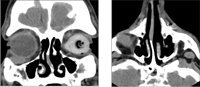

La TAC orbitaria identificó una tumoración ovalada de 6,8x13, 3x14, 1mm, en región supero-externa del globo ocular derecho de una densidad similar a partes blandas, con aspecto moderadamente heterogéneo sugestivo de proceso expansivo (Figura 1). Dados los antecedentes patológicos del paciente y el crecimiento agudo de la lesión se decidió realizar biopsia excisional (Figura 2). La tumoración era de un tejido elástico con límites mal definidos. No invadía los músculos recto inferior, ni recto lateral y respetaba el globo ocular (Figura 3). El material obtenido se etiquetó de sarcoma fusiforme grado 3. Dada la baja supervivencia de esta entidad, se valoró conjuntamente con el comité de oncología y se decidió plantear cirugía radical: exanteración. El paciente rechazó la misma y siguió controles posteriores. Ocho meses después el paciente seguía libre de enfermedad con estudio de PET-SCAN negativo.

Figura 1. TAC orbitaria corte coronal y sagital: En la región infero-externa del globo ocular derecho se observa una imagen ovalada de densidad similar a partes blandas con aspecto heterogéneo